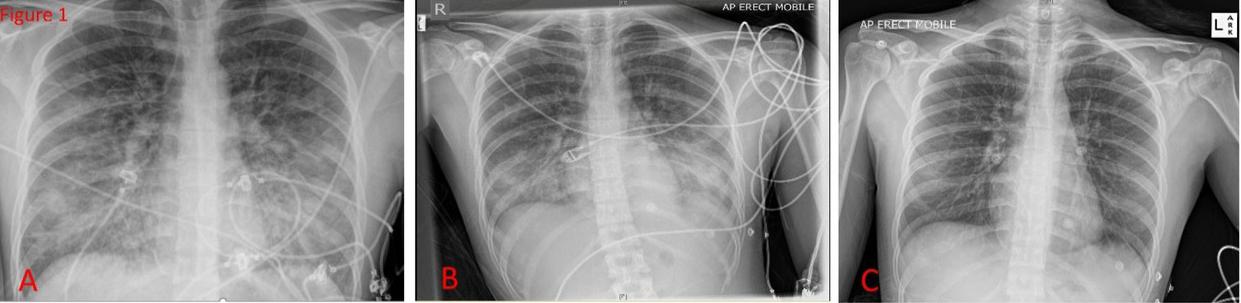

On day three post-admission, there was complete resolution of the previous opacifications on her chest x-ray (Figure 1), and she was discharged home.

Fig. 1

Serial AP Chest-Xrays. A. On admission on non-rebreather mask. B. Day 1 of admission on high flow nasal prongs. C. Day 3 of admission on room air when patient was discharged.